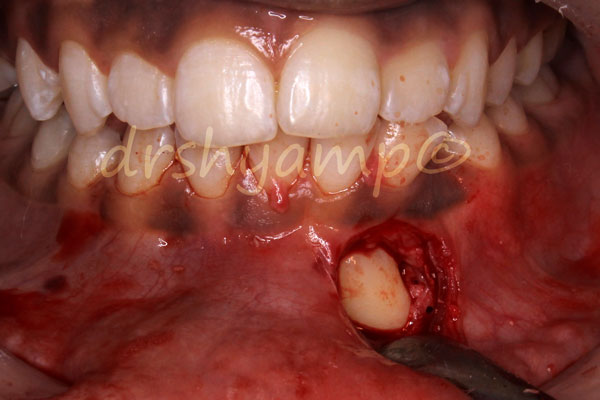

Disimpaction of Impacted canine

Disimpaction of Impacted canine

Disimpaction of Impacted canine

Disimpaction of Impacted canine

Disimpaction of Impacted canine

Disimpaction of Impacted canine

Disimpaction of Impacted canine

Disimpaction of Impacted canine

Disimpaction of Impacted canine

Disimpaction of Impacted canine

Disimpaction of Impacted canine

Disimpaction of Impacted canine

Disimpaction of Impacted canine

Disimpaction of Impacted canine

Disimpaction of Impacted canine

Disimpaction of Impacted canine